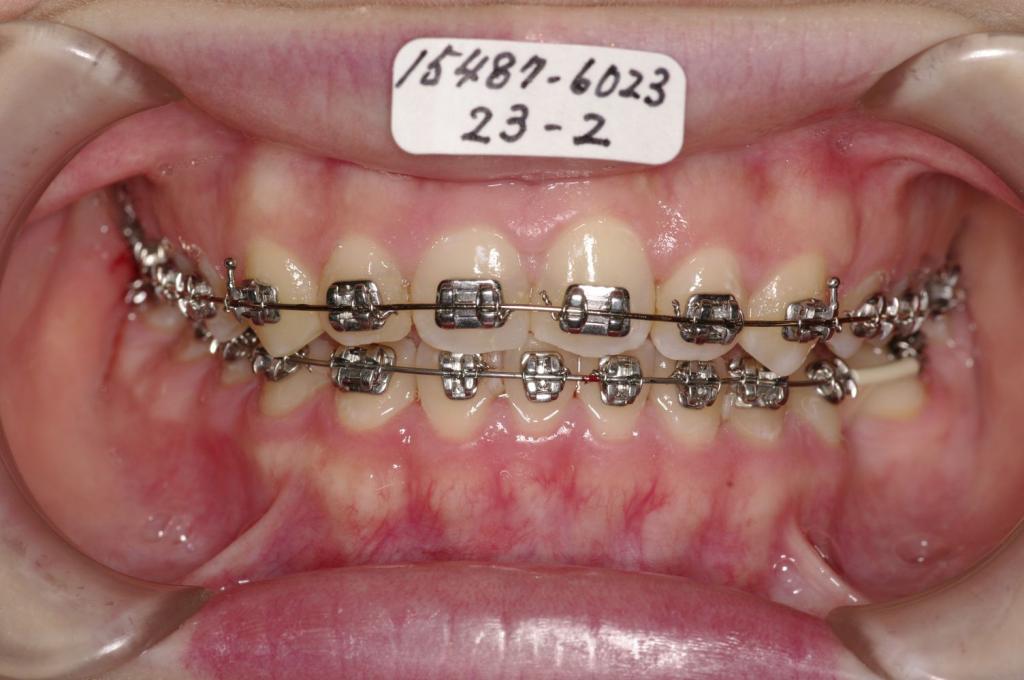

- 歯並び・咬み合わせ・八重歯・乱杭歯の矯正治療

- 前歯2本の方向